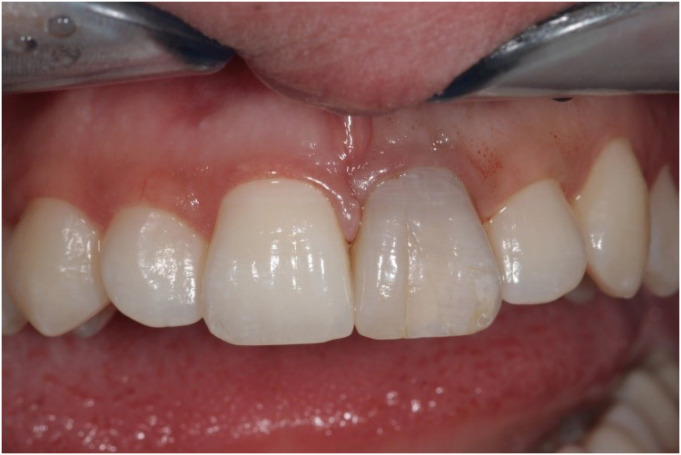

A 20-year-old woman with a history of root canal treatment of the upper maxillary (left) central incisor was referred to our department from a private clinic. The root canal treatment had been initiated 4 months prior but could not be finished. A clinical examination revealed a temporary filling on the palatal surface. The coronal part of the tooth was discolored, and multiple visible cracks were present on the buccal surface (Figure 1). The tooth was asymptomatic; the mobility was normal, and the probing depth at all sites was ≤ 3 mm. A periapical radiograph revealed a lesion around the apex and an enlarged and clearly irregular root canal (Figure 2A). When specifically asked, the patient denied knowledge of any previous dental trauma. Upon checking the electronic documentation of the faculty of the institution, we found that the patient had visited the department 2 years prior for other reasons, and X-rays were taken at that appointment. From a comparison of the periapical X-rays, it was clear that something must have happened since her last visit (Figure 2B). After gaining her confidence, the patient and her mother admitted that the patient had suffered from domestic abuse at the hands of her boyfriend, but that had been taken care of by the police. At this point, a small-field-of-view high-resolution cone-beam computed tomography (CBCT) scan was taken to investigate the extent and irregularity of the lesion. The scan confirmed the presence of a periapical lesion, which had destroyed most of the buccal bony wall around the root. The scan also showed massive internal resorption inside the root canal (Figure 2C). The patient was informed of the findings and the poor prognosis of the tooth, but since she desperately wanted to keep her tooth, she provided consent for endodontic treatment, which was initialized at a later appointment. The patient was also informed that due to the irregular nature and more pronounced buccolingual extent of the resorptive lesion and the massive destruction of the buccal bony plate, which cannot be seen or monitored on periapical X-rays, it would be beneficial to control the steps of the treatment and perform the monitoring via CBCT scans. The patient was informed of the extra radiation exposure resulting from the CBCT scans, but she insisted on undergoing scans instead of periapical X-rays when deemed beneficial by the clinicians.

Figure 1

Photograph of the patient upon presentation.